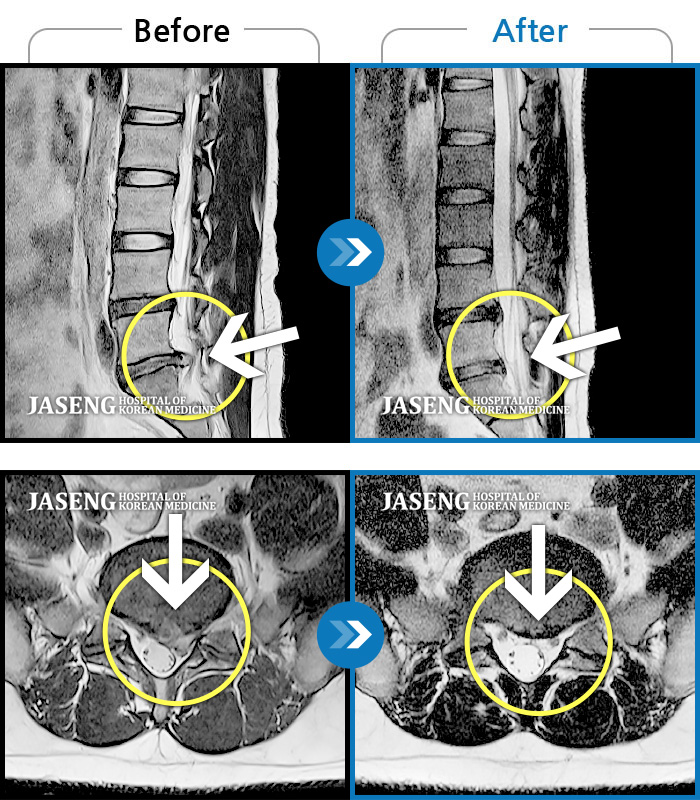

허리디스크

많이 본 사례

인천 · 조남훈 원장

계속 아파서 일을 일주일에 2번밖에 못해요.

촬영시기

2019.11.23 ~ 2023.12.15

2023.12.20

조회수 445